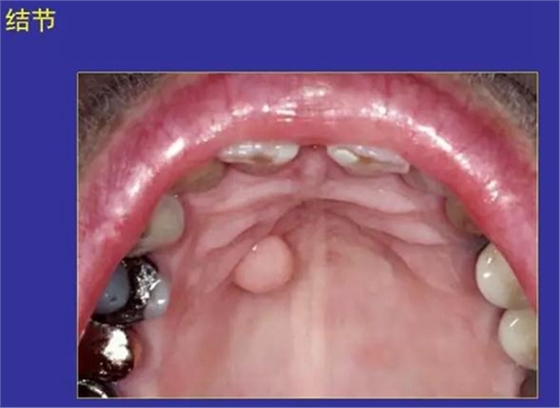

11.結節(jié):突起或突起于口腔黏膜的實體病損。

纖維瘤、痣

正常口腔黏膜及常見病損圖